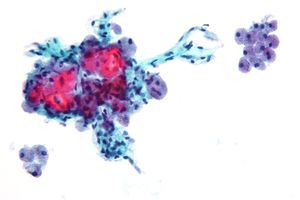

صورة مجهرية لسرطان الغدة الدرقية الجريبي توضح موقع نمو السرطان عبر الكبسولة الجريبية. | |

من غير الممكن التمييز بين الأورام الجريبية الحميدة والسرطانية على أسس خلوية. إذا أشارت نتائج الخزعة بالإبرة الدقيقة إلى وجود ورم جريبي، فينبغي في تلك الحالة استئصال الفص الدرقي للقيام بتشخيص للأنسجة. ومن السمات المميزة لسرطان الغدة الدرقية الجريبي التوغل الكبسولي والوعائي للخلايا السرطانية. ومع ذلك، يجب تقييم نقاط التركيز في التوغل الكبسولي بعناية وتمييز التمزق الكبسولي الناتج عن الخزعة والذي يؤدي إلى WHAFFT (worrisome histologic alterations following FNA of thyroid).